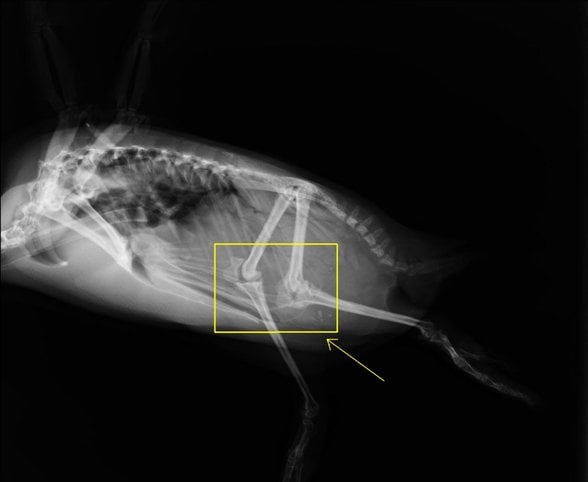

Mesela devekuşlarında da aynı durum var:

:sharpen(0.5,0.5,true)/old%2Fqna_media%2F9b53811334c2b63b9a9f9e7ec665fc4f.jpeg)

O bacağın ortasında, arkaya doğru çıkıntı yapan şey diz değil, bilek! Diz, vücudun içine gömülmüş halde.